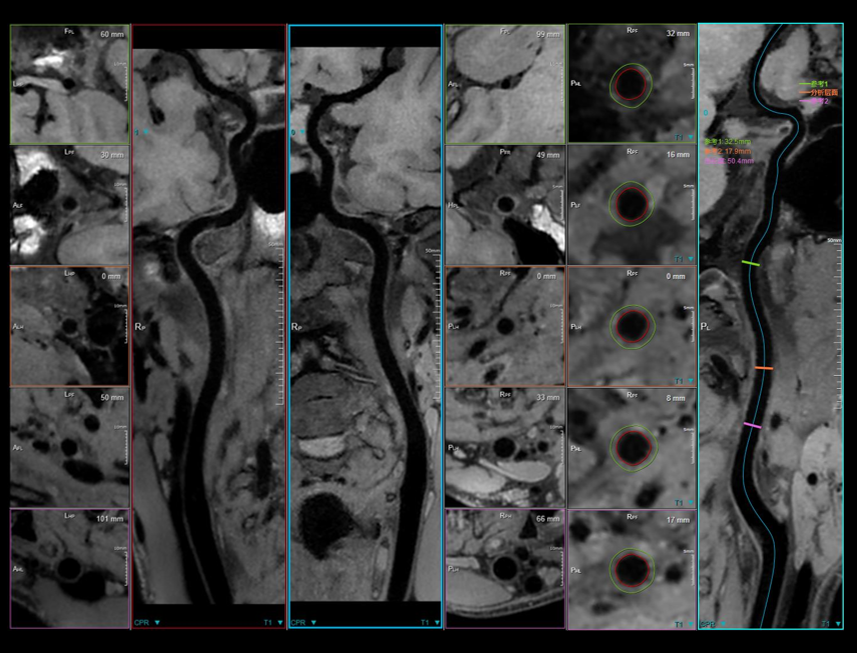

60 cm 超大视野腹部 T2W